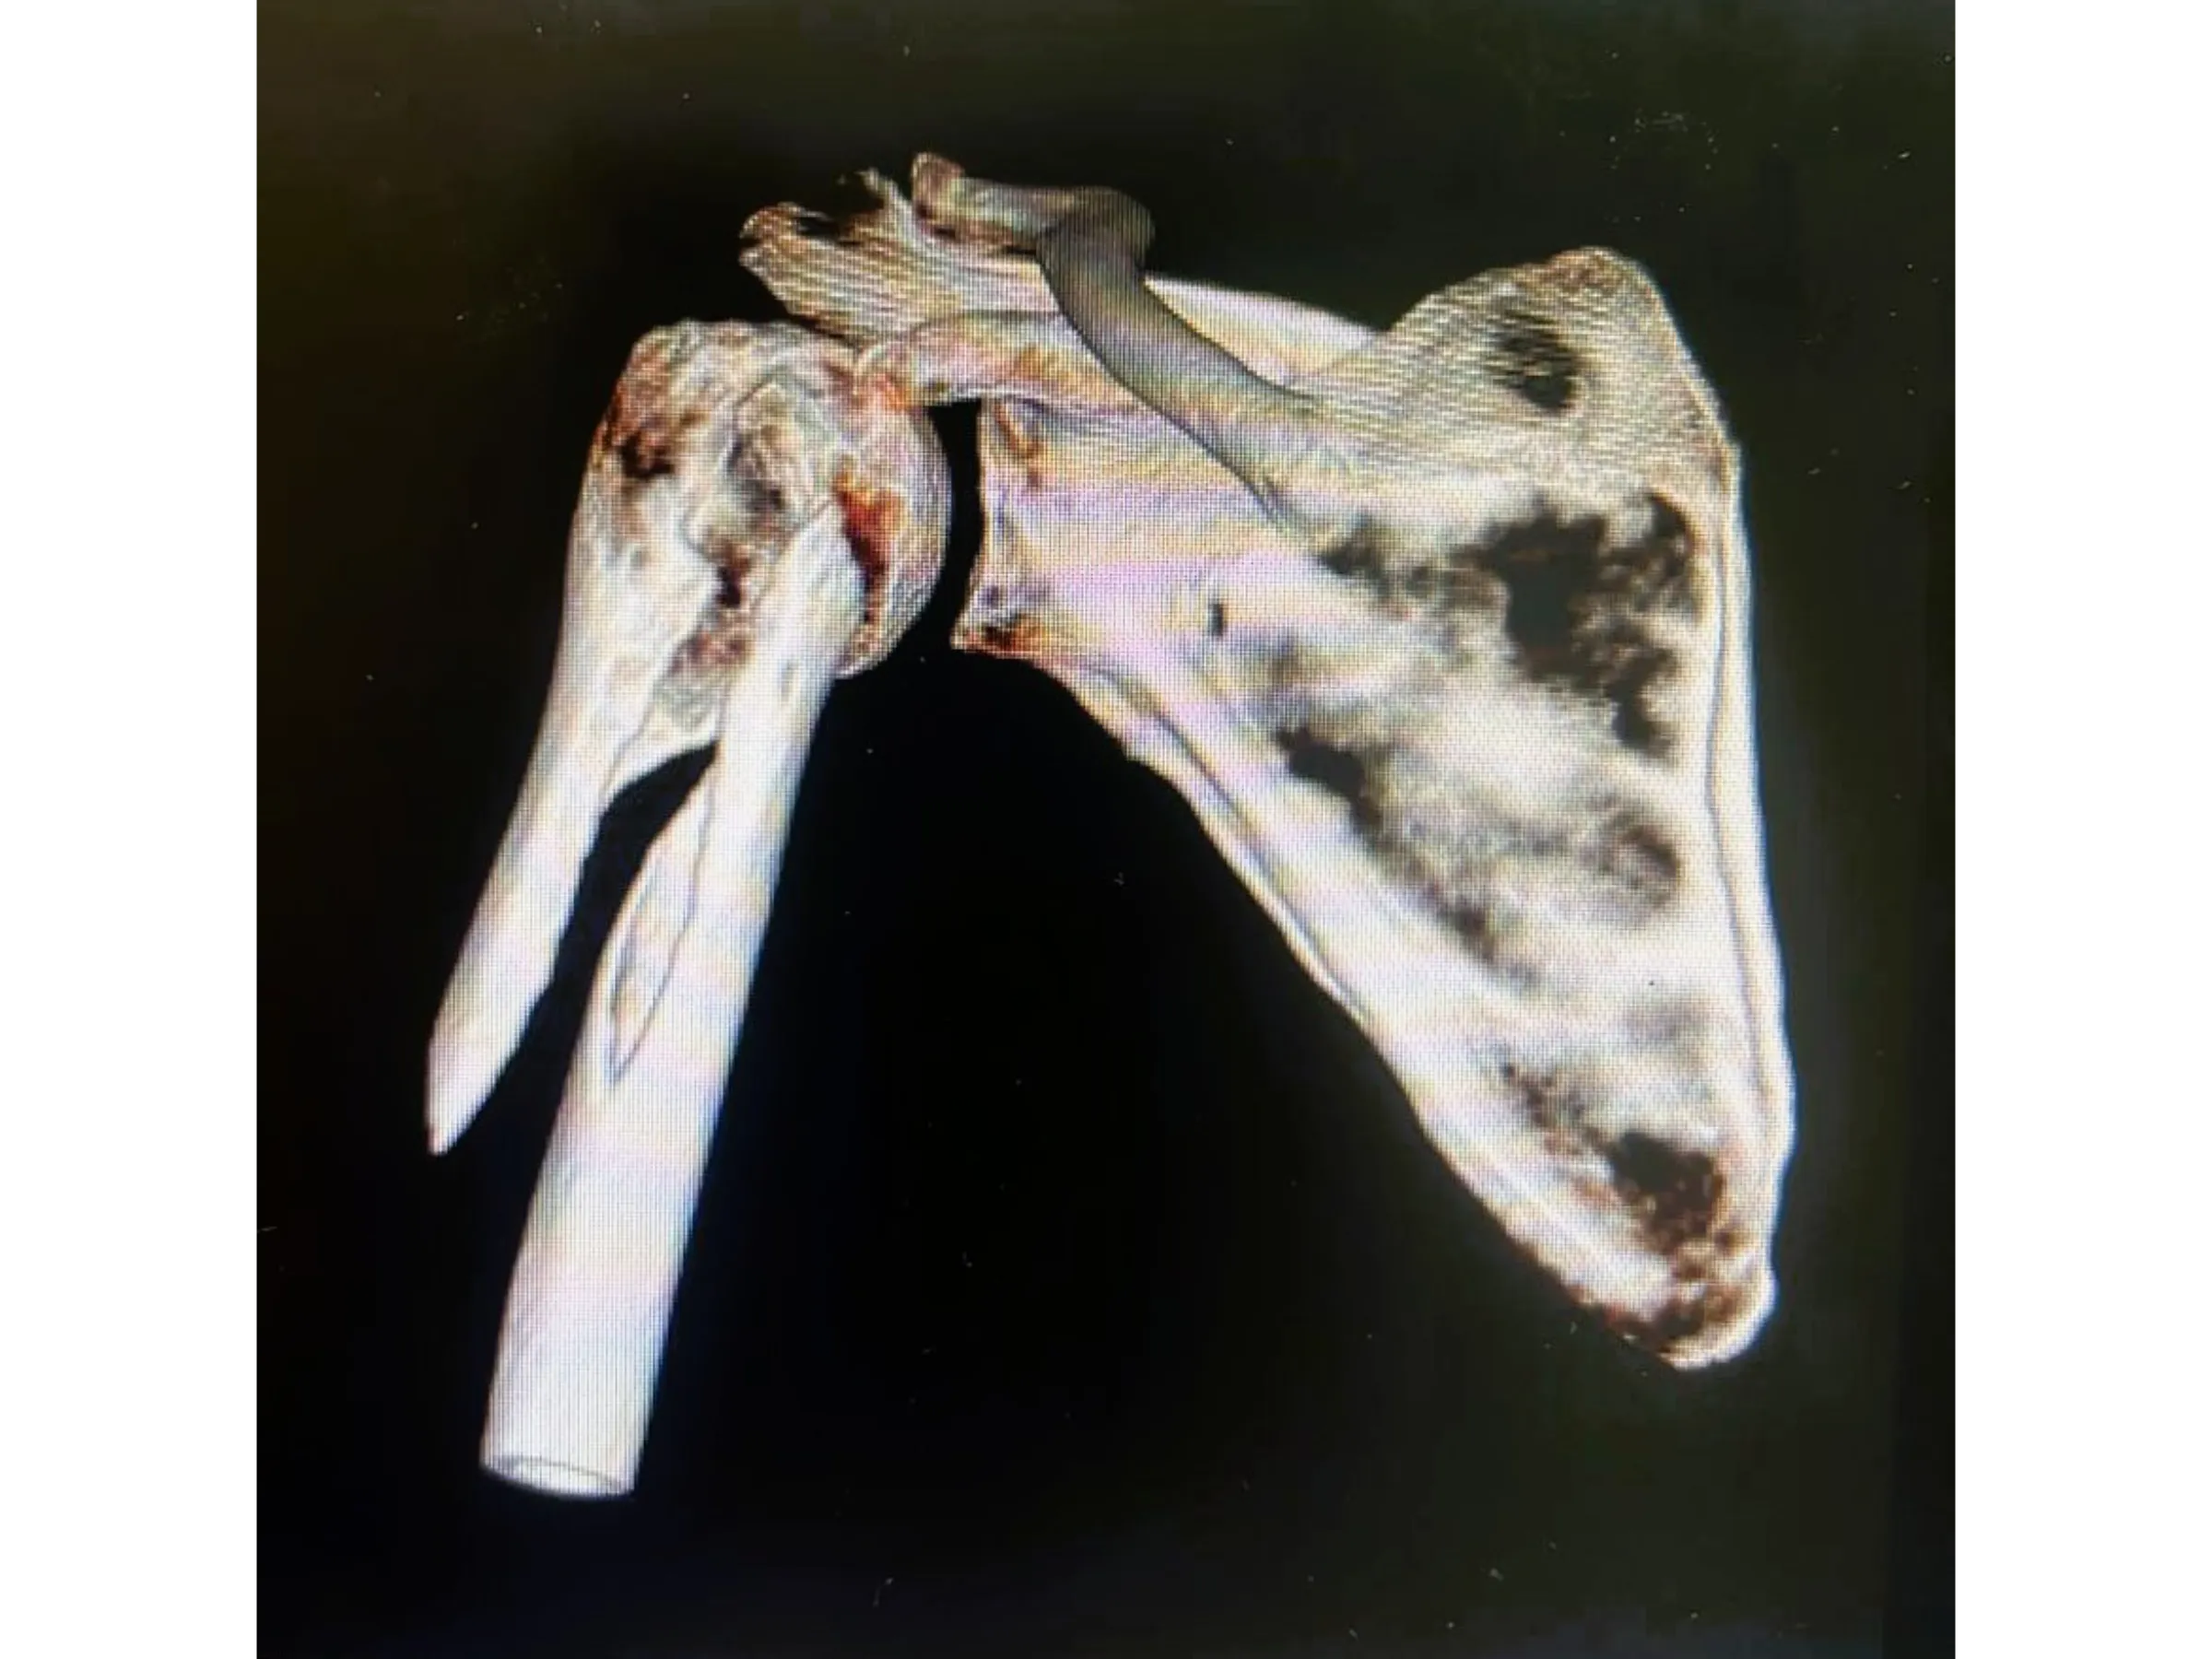

Proximal humerus fractures in elderly patients require effective stabilization with minimal tissue damage. This training presents a fluoroscopy-guided surgical approach using a long intramedullary nail that preserves the rotator cuff and ensures secure fixation. The technique is demonstrated step-by-step from a surgical perspective, focusing on anatomical and biomechanical precision.

- Stable Intramedullary Fixation: Insertion of a long rod with multiple locking screws, including metaphyseal screws.

- Rigorous Fluoroscopic Control: Anteroposterior and lateral images to ensure parallelism and precision of the implants.